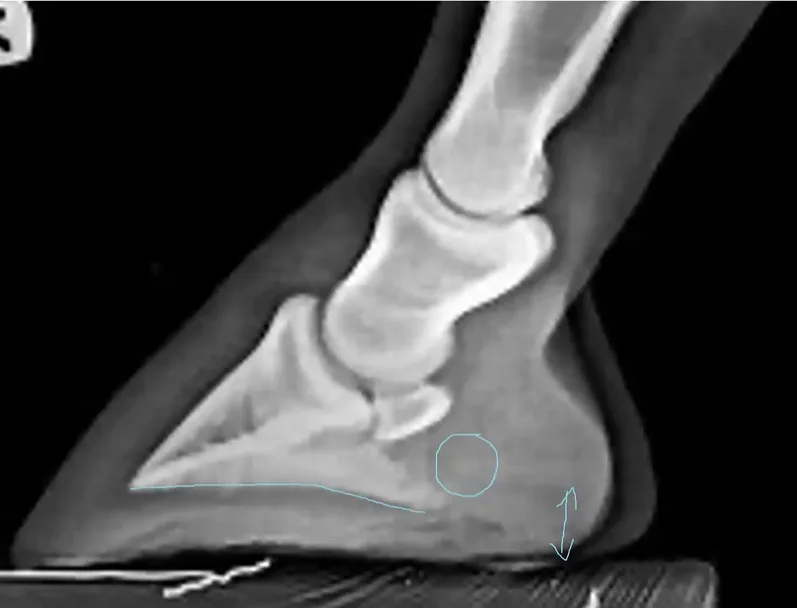

Frog engagement

When we have any degree of prolapse of the caudal hoof structure (described and discussed in depth in previous articles and webinars), this migration of the soft tissue structures of the back half of the hoof in response to gravity predisposes to negative changes to PA. Conversely, if prolapse is mitigated using pads and/or packing, this will have a direct positive effect on PA. While there will be some linear relationship with the corresponding CA maintained, further research needs to establish how much change to PA by way of these mechanisms happens, isolated from changes to CA.

Figure 7. An example of morphological changes to the soft tissues of the back of a front foot. These changes could create changes to the relationship between CA and PA as digital cushion development could change PA isolated from CA changes.